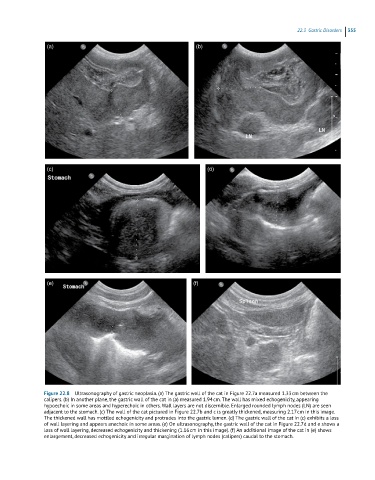

Figure 22.8 Ultrasonography of gastric neoplasia. (a) The gastric wall of the cat in Figure 22.7a measured 1.33 cm between the

calipers. (b) In another plane, the gastric wall of the cat in (a) measured 1.94 cm. The wall has mixed echogenicity, appearing

hypoechoic in some areas and hyperechoic in others. Wall layers are not discernible. Enlarged rounded lymph nodes (LN) are seen

adjacent to the stomach. (c) The wall of the cat pictured in Figure 22.7b and c is greatly thickened, measuring 2.17 cm in this image.

The thickened wall has mottled echogenicity and protrudes into the gastric lumen. (d) The gastric wall of the cat in (c) exhibits a loss

of wall layering and appears anechoic in some areas. (e) On ultrasonography, the gastric wall of the cat in Figure 22.7d and e shows a

loss of wall layering, decreased echogenicity and thickening (1.16 cm in this image). (f) An additional image of the cat in (e) shows

enlargement, decreased echogenicity and irregular margination of lymph nodes (calipers) caudal to the stomach.